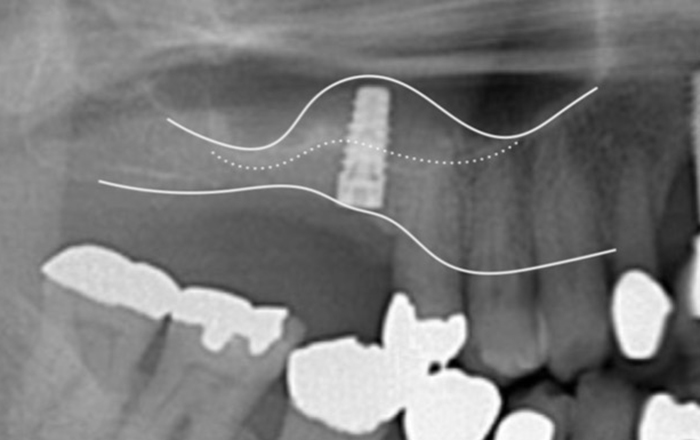

サイナスリフト(ラテラルアプローチ)とは、上顎洞頬側骨壁に穴をあけ、上顎洞粘膜(シュナイダー膜)を洞底部から剥離して挙上し、その挙上スぺースに骨補填材を移植することにより上顎洞底部の骨造成をはかり、インプラントを埋入できるだけの骨を造成する方法です。

インプラント を入れるだけの骨がほとんどない場合でも上顎洞の中に骨を造成できる治療法になりますが、シュナイダー膜がやぶれて移植した骨が感染してしまいインプラント ができなくなってしまう可能性もあります。

ソケットリフトと比較して外科侵襲は大きくなりますが、確実に大量の骨を造成することができるようになります。